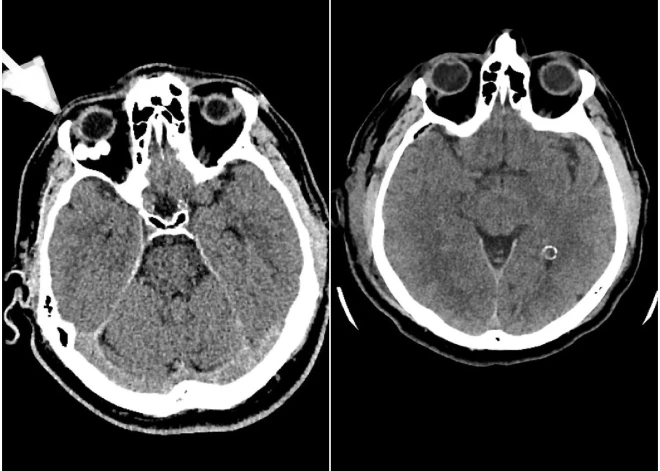

Paula Stradiņa Klīniskās universitātes slimnīcas (PSKUS) Neiroķirurģijas klīnikā 7.janvārī veikta unikāla un ārkārtīgi reta operācija pacientam ar neparastu patoloģiju – blīvu, kalcinētu veidojumu acs dobumā aiz acs ābola, ziņo PSKUS sabiedrisko attiecību daļas vadītāja Vineta Kļaviņa.

Pacients ilgstoši sūdzējās par redzes dubultošanos, spiediena sajūtu labajā acī un acs ābola kustību traucējumiem, bet neskatoties uz simptomiem, redze bija saglabāta. Padziļināti izmeklējumi atklāja ļoti retu, kalcinētu veidojumu, kas saspieda acs muskuļus un nervus, izraisot neiroloģiskos simptomus.

Operācijas laikā neiroķirurģijas komanda veica augstas precizitātes ķirurģisku iejaukšanos – caur galvaskausu tika izveidota aptuveni vienu centimetru liela atvere acs dobuma sienā, kas ļāva piekļūt patoloģiskajam veidojumam un veikt tā pilnīgu rezekciju, nebojājot acs struktūras.